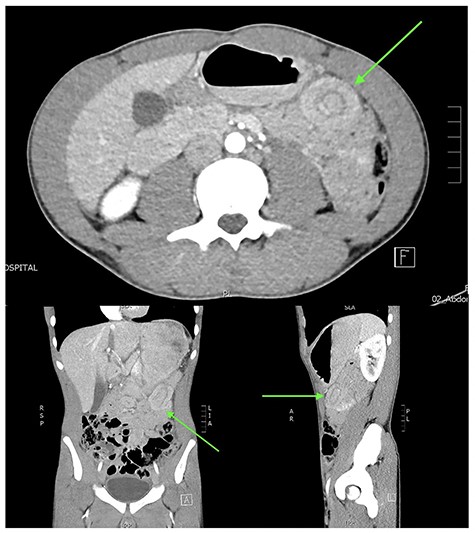

A normally fit and well 15-year-old male presents after being pinned between a tree and a car at low speed. He has no loss of consciousness and self-extricates on scene. On arrival, he is alert and haemodynamically stable. He has minor bruising to his upper abdomen and no other external injuries. His abdominal examination is reassuring with no peritonism. His biochemistry is normal with a haemoglobin of 143 g/L and a lactate of 1.2 mmol/L. An abdominal focussed assessment with sonography in trauma (FAST) scan is positive for free fluid. The patient remains stable and proceeds to contrast-enhanced abdominal computed tomography (CT), which reveals small volume haemoperitoneum and a hyperdense focus 45 × 31 × 30 mm between bowel loops left mid-abdomen in keeping with interloop mesenteric haematoma, abutting the base of a 5 cm length of entero-enteric intussusception (Fig. 1). Adjacent small bowel loops are thick walled, with no evidence of obstruction or perforation.

Abdominal CT in axial, coronal and sagittal planes demonstrating mesenteric haematoma and jejuno-jejunal intussusception (‘bowel-within-bowel’ sign indicated by green arrow).